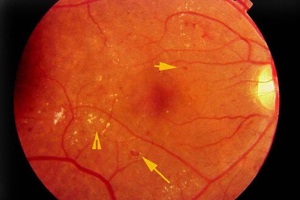

Діабетична ретинопатія – мікроангіопатія судин сітківки ока при цукровому діабеті, що призводить до зниження зору, а в термінальній стадії – до повної втрати зору. Часто спостерігається у дітей підліткового віку.